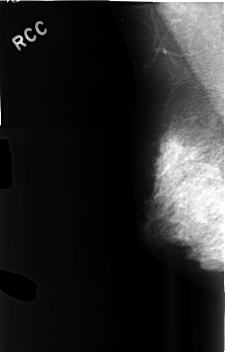

C_0486_1.RIGHT_CC

RIGHT_CC LINES 4576 PIXELS_PER_LINE 2952 BITS_PER_PIXEL 12 RESOLUTION 50 NON_OVERLAY